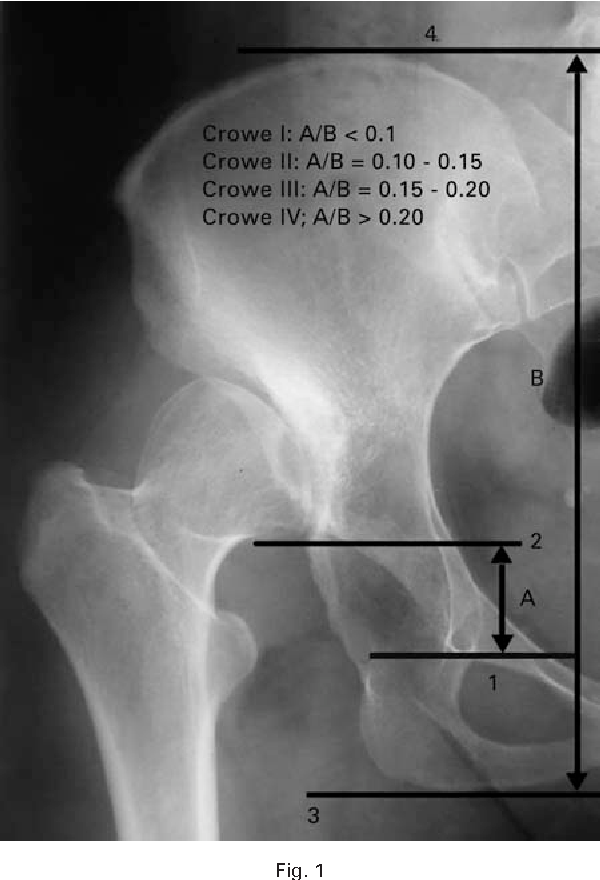

(1) 第一种分型,Crowe分型,

早在1979年,美国学者Crowe就发表了文章对髋臼发育不良(先髋,DDH)严重程度进行分型,以便于规范先髋的治疗和同行之间的交流。

髋臼发育不良Crowe分型

X线片显示用于定义Crowe分类的标准。距离A是骨盆的总高度(坐骨结节和髂嵴之间的垂直距离)。距离B是在股骨头与股骨颈的交界处和髋臼泪滴之间距离。Crowe根据以百分比(B/A)表示的股骨头近端移位对髋关节发育不良的严重程度进行分类。Crowe 1型 = B/A < 0.1或股骨头脱位<50%,Crowe II型 = B/A 0.10-0.15或股骨头脱位50-75%,Crowe III型 = 0.15-0.20或股骨头脱位>75%,Crowe IV型 = B/A > 0.20或股骨头脱位>100%.